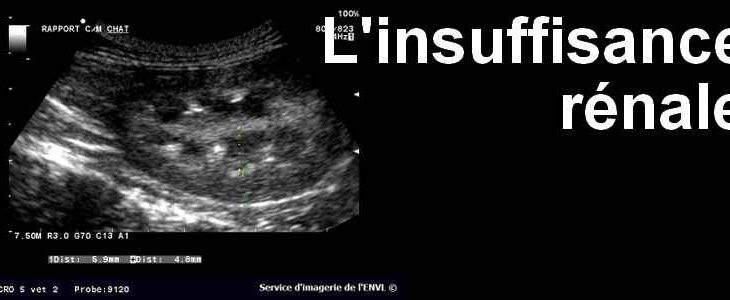

Insuffisance rénale : « j’ai décidé d’arrêter la dialyse, je n’en pouvais plus »

Vincent Ouédraogo, jeune enseignant a été diagnostiqué insuffisant rénal en 2020. Chaque séance de dialyse lui coûte 95000F CFA. « Je devais le faire au moins 2 à 3 fois par semaine. J’ai dû suivre la dialyse jusqu’à un certain moment où je n’en pouvais plus », dit-il. Comme Vincent, plusieurs malades d’insuffisance rénale manquent de moyens financiers pour suivre les soins. Studio Yafa · « Je n’en pouvais plus, j’ai décidé d’arrêter la dialyse » ( MiniMag 8/6/21) [...]